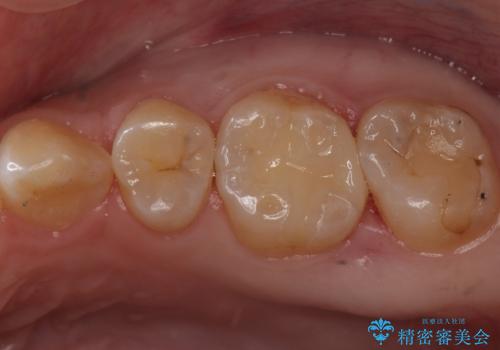

歯と歯の間によくものが詰まる。。セラミック治療

銀の詰め物を白い物にしたい